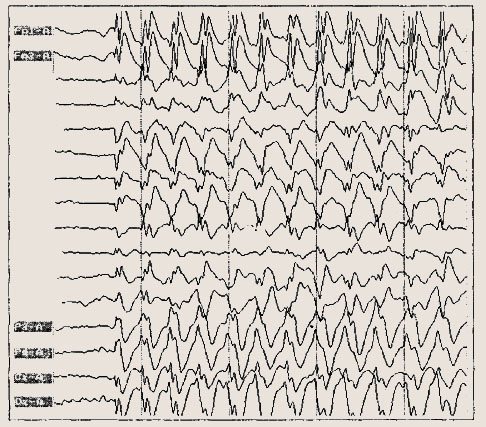

Диагноз основывается на типичных проявлениях приступов и ЭЭГ данных. На нормальном или умеренно измененном общем фоне ЭЭГ имеются локальные пики или острые волны и/или комплексы пик-волн в одном полушарии или двух, но с односторонним преобладанием в центрально-средневисочных отведениях.

Типичная роландическая активность в левом полушарии. Скорость — 30 мм/с. Амплитуда уменьшена в 2 раза.

рактерно извращение фазы над роландической или височной областью. Эпиактивность может иногда отсутствовать, их выявлению помогает подготовка с частичной депривацией сна.